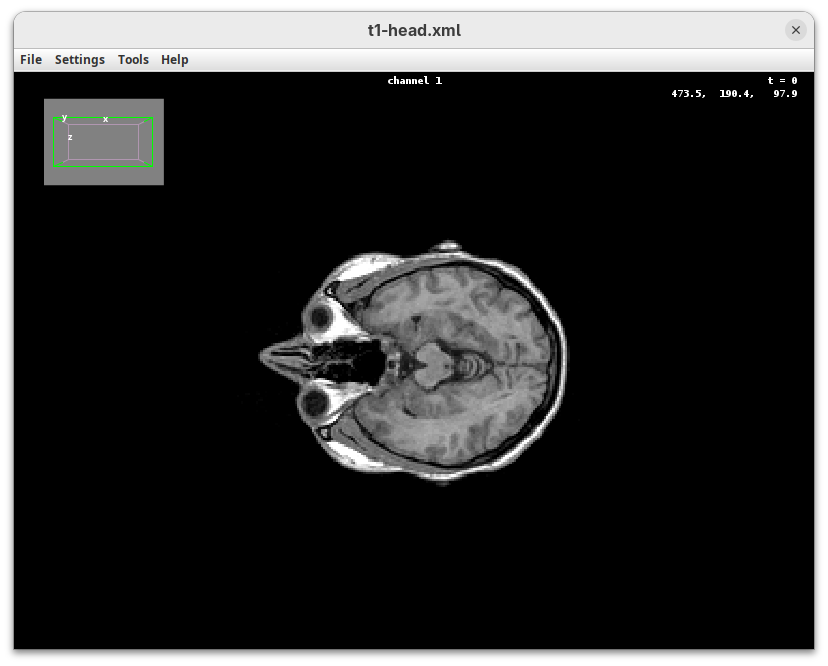

BigDataViewer (Pietzsch et al. 2015) is one of the most important tools for visualizing large, multidimensional datasets. It provides a simple and intuitive interface and shortcuts to swiftly navigate through your sample even on a regular laptop. This is possible because of the underlying file format used by BigDataViewer: the XML/HDF5 combo. Therefore, before opening the plugin, we must convert our dataset.

Plugins>BigDataViewer>Open XML/HDF5and select thet1-head.xml.

The BigDataViewer interface will open showing an optical section of the head sample.

Getting familiar with BigDataViewer is an essential skill for navigating large 3D datasets. It’ll also be important for the multiview registration pipeline. So, take the time to learn the basic commands and shortcuts. It is nicely intuitive. The BigDataViewer’s page on the ImageJ Docs has the official documentation and we can also go to Help > Show Help for an up-to-date overview.

Some of the movements to try:

Left-click and drag: turn the sample around the mouse pointer at any arbitrary angle.Right-click and drag: move the sample in the XY plane (of the view).Scroll: move through the Z plane (of the view). UseShift+Scrollto move fast.Ctrl+Shift+Scroll: zoom in or out.

But, most importantly, are the commands to put your sample back to its original orientation or along any of the original dimension axes:

Shift+Z: orient the sample on the XY plane.Shift+X: orient the sample on the ZY plane.Shift+Y: orient the sample on the ZX plane.

Finally, a visual tip. The default interpolation between image slices is nearest-neighbors. Press I to activate the tri-linear interpolation to obtain a much smoother (and improved) data visualization.